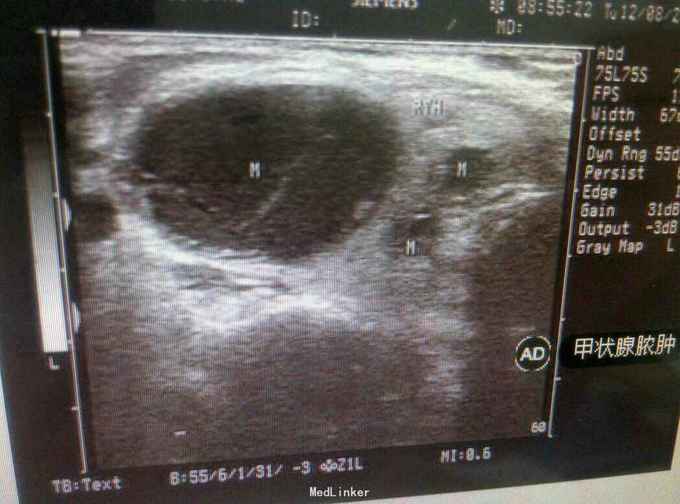

查体:气管右移,颈前区偏左可触及一约3.1cm×2.0cm大小肿物,质韧,表面光滑,边界清楚,活动度好,有压痛,有囊性感,可随吞咽上下活动。 辅查:超声检查:甲状腺左叶内低回声结节,周界清,内少许无回声区,诊断甲状腺腺瘤囊性变。 影像学诊断:甲状腺脓肿